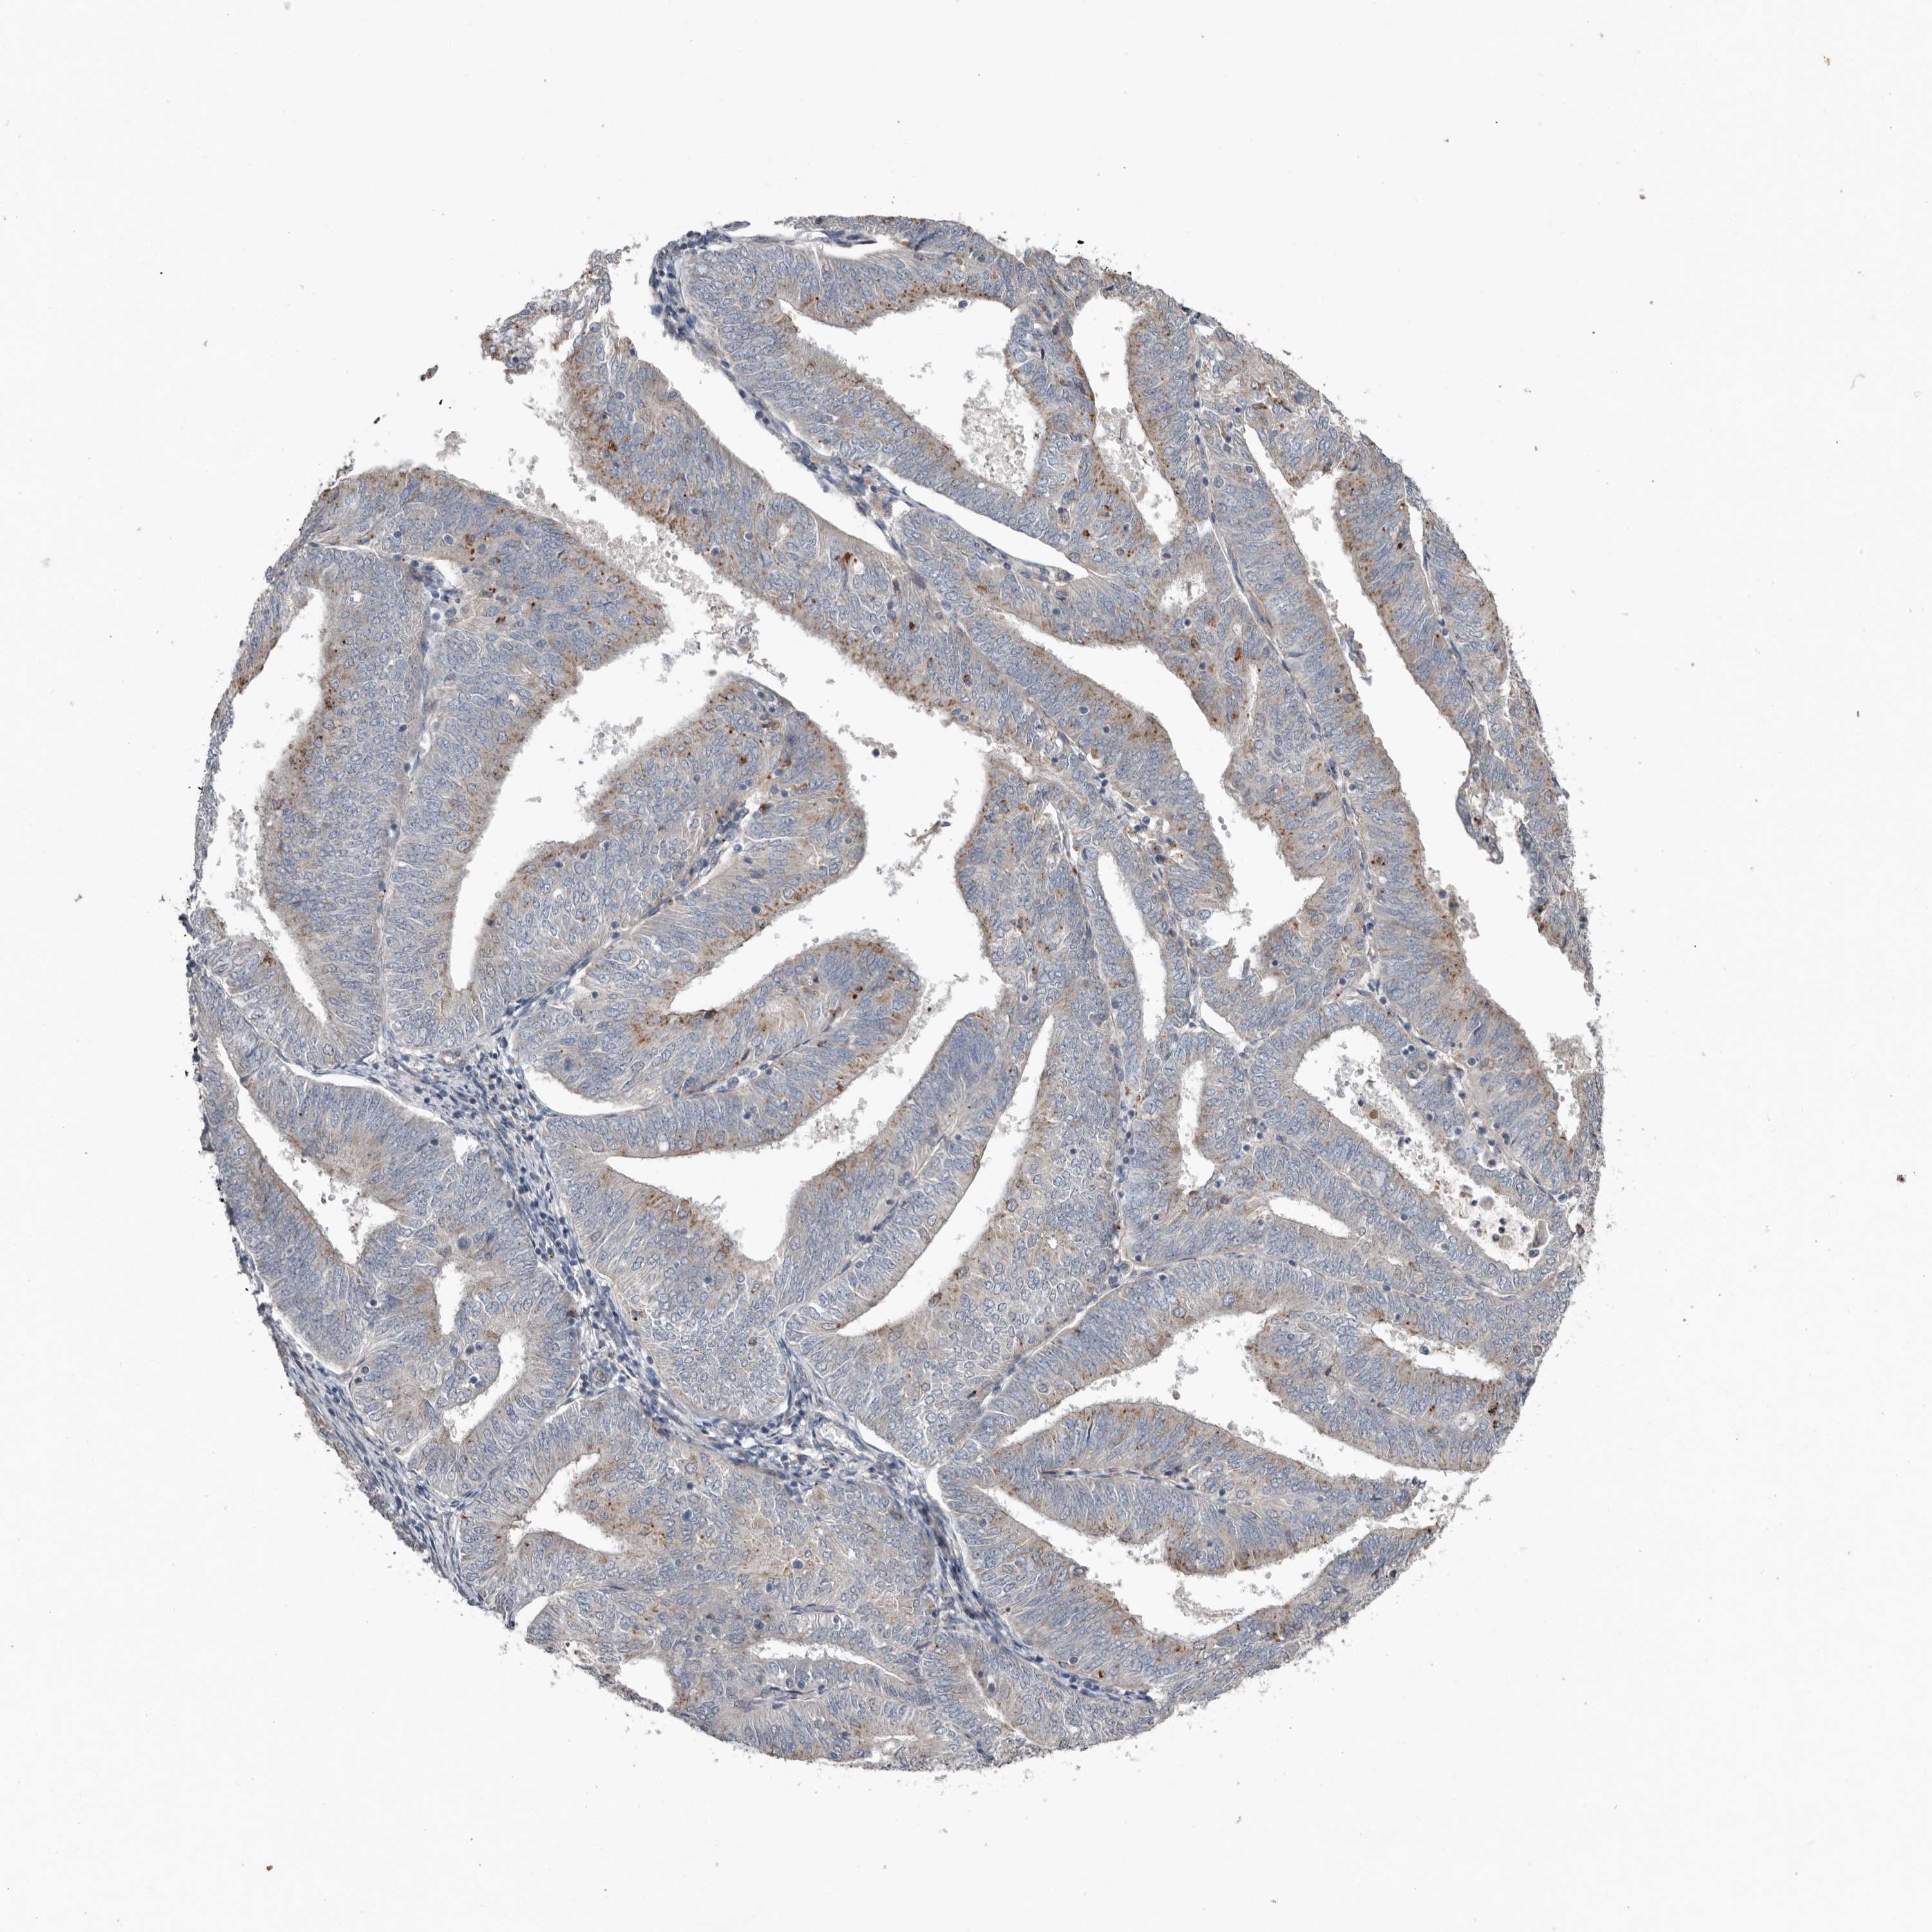

RANBP17